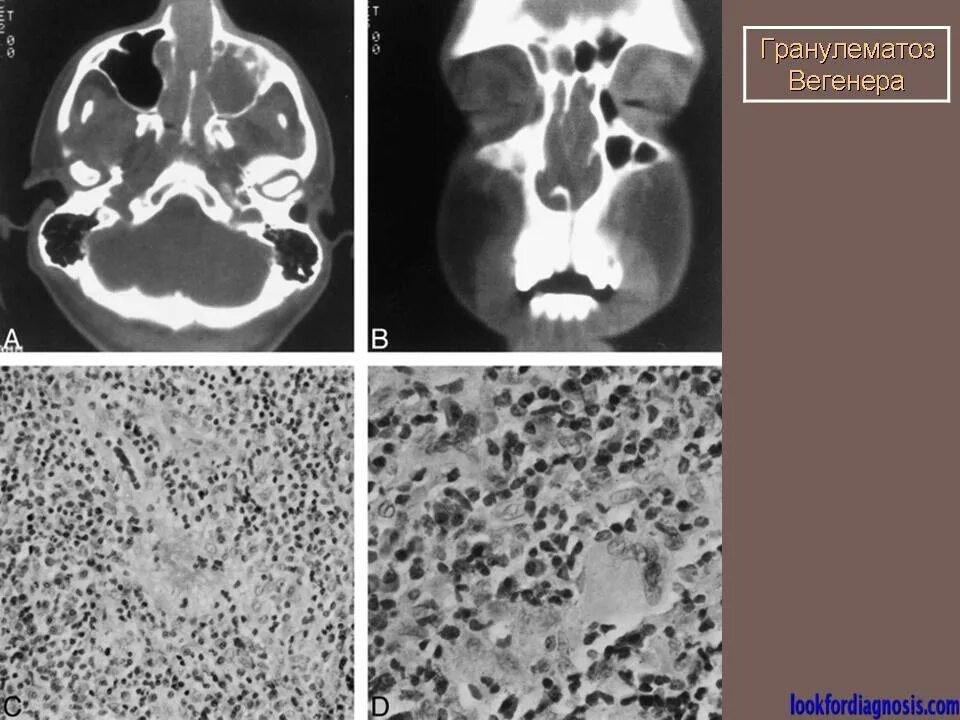

Гранулематоз лечение